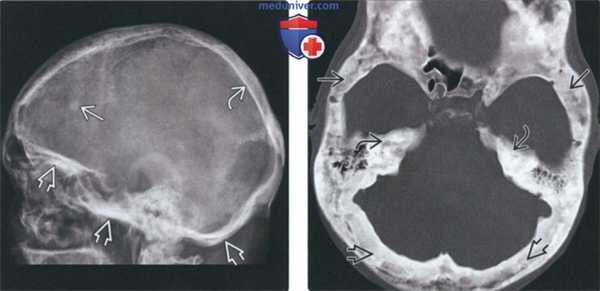

(Слева) На рентгенограмме черепа в боковой проекции определяется БП основания черепа и височной кости. Визуализируется очаг в лобной кости (в виде «хлопковой ваты») на фоне остеосклероза и утолщения кортикальной пластинки теменной кости.

(Справа) На аксиальной КТ в костном окне определяется смешанная фаза БП с диффузным поражением свода и основания черепа. Структура чешуи височных костей и затылочных костей тотально изменена в виде «хлопковой ваты».